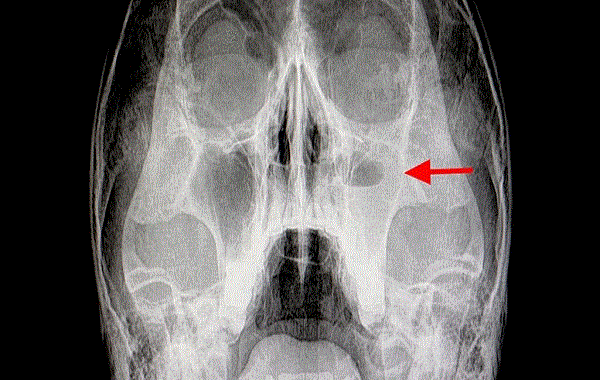

Chronic rhinosinusitis, which causes a persistent blocked nose and headaches among other symptoms, affects 11 percent of people in the US – and recent research has found a link between the condition and changes in brain activity.

The researchers tapped into data from the Human Connectome Project to find 22 subjects living with chronic rhinosinusitis and 22 control subjects with no sinus inflammation. Data from fMRI scans were then used to compare blood flow and neuron activity in the brain.

The differences were more significant in people with more severe rhinosinusitis, the team noted. Taken together, these increased and decreased spots of activity in the brain could be behind the symptoms people report.